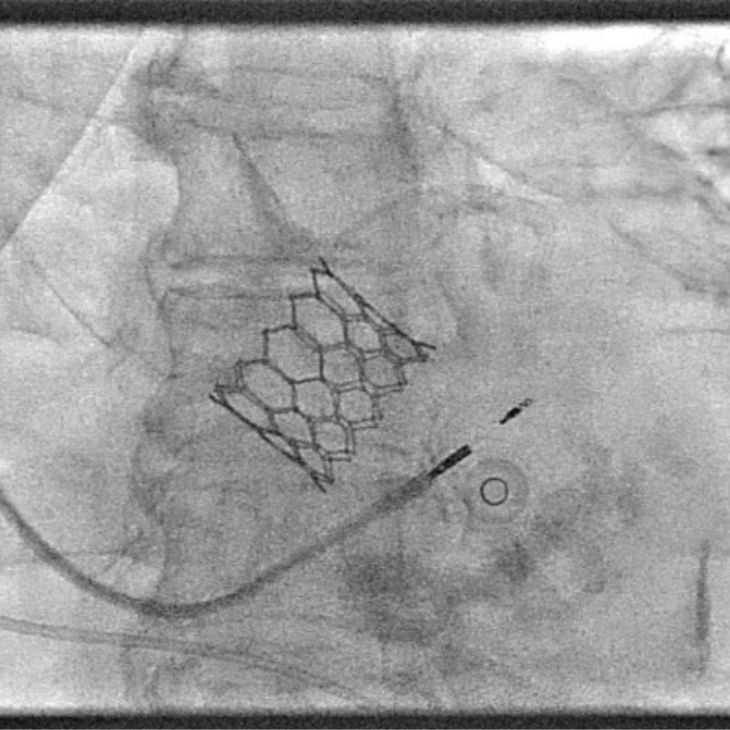

TAVI is a minimally invasive procedure to replace a narrowed aortic valve without open-heart surgery. Dr Sayan Sen offers expert transcatheter valve replacement from specialist cardiology centres in London for patients with severe aortic stenosis.

TAVI (Transcatheter Aortic Valve Implantation) is a procedure to replace a diseased aortic valve using a catheter-based approach, without the need for major surgery. It’s primarily used for patients with severe aortic stenosis.

A new valve is delivered through a blood vessel (usually via the groin) and positioned within the existing narrowed valve. Once in place, the replacement valve takes over blood flow control. TAVI offers a faster recovery, making it suitable for patients who may not be eligible for traditional open-heart valve surgery.

TAVI is usually performed under light sedation or local anaesthetic. You may remain awake but relaxed and pain-free. In some cases, general anaesthesia may be used. The procedure is carried out in a specialised cardiac catheter lab with advanced imaging to guide precise valve positioning.